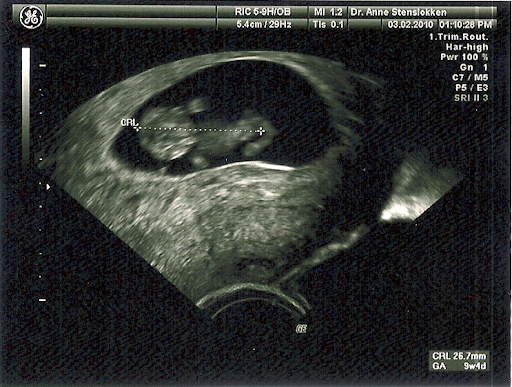

lin76 Skrevet 6. februar 2010 #1 Skrevet 6. februar 2010 Tok privat UL på onsdag, her er bildene. Vanleg 2d: http://lh3.ggpht.com/_Fdwf2By3WkI/S2mzT5lq5uI/AAAAAAAAJmU/y1aXJFyHDGo/ultralyd%202d%20030210.png Og 3d: http://lh5.ggpht.com/_Fdwf2By3WkI/S2mzN33gDnI/AAAAAAAAJmM/uS-WKyHiDSE/ultralyd%203d%20030210.png Ifølge mine berekningar var eg 10+1 onsdag, ifølge størrelsen på fosteret (28mm) var eg 9+5 då. Spelar lita rolle, så lenge alt såg veldig bra ut. Hjertet banka og banka, og den litle peanøtta sprella vilt med beina. Tok for øvrig UL på Balderklinikken i Oslo, det kosta 980 kroner og gynokologen var veldig flink og hyggeleg.